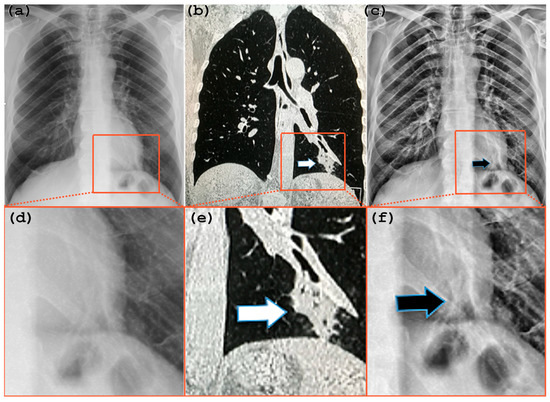

3. Description and Performance Evaluation of the Algorithm

4.2. Radiological Evaluation and Statistics